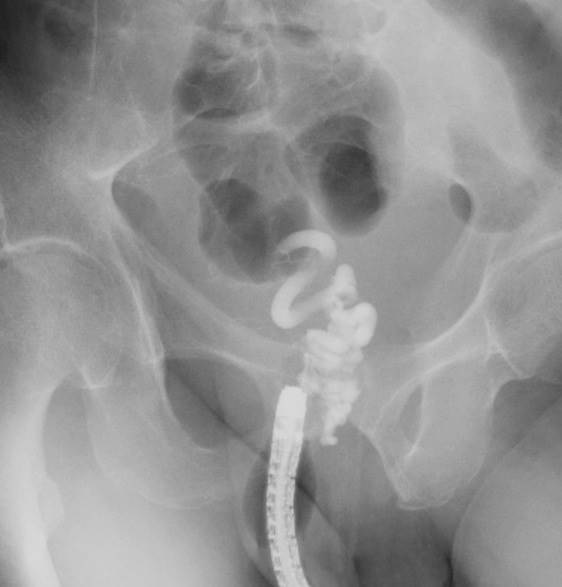

Figure 2: Fluoroscopic observation with infusion of 5% EOI was performed to determine the extent of the varices.

figure 2